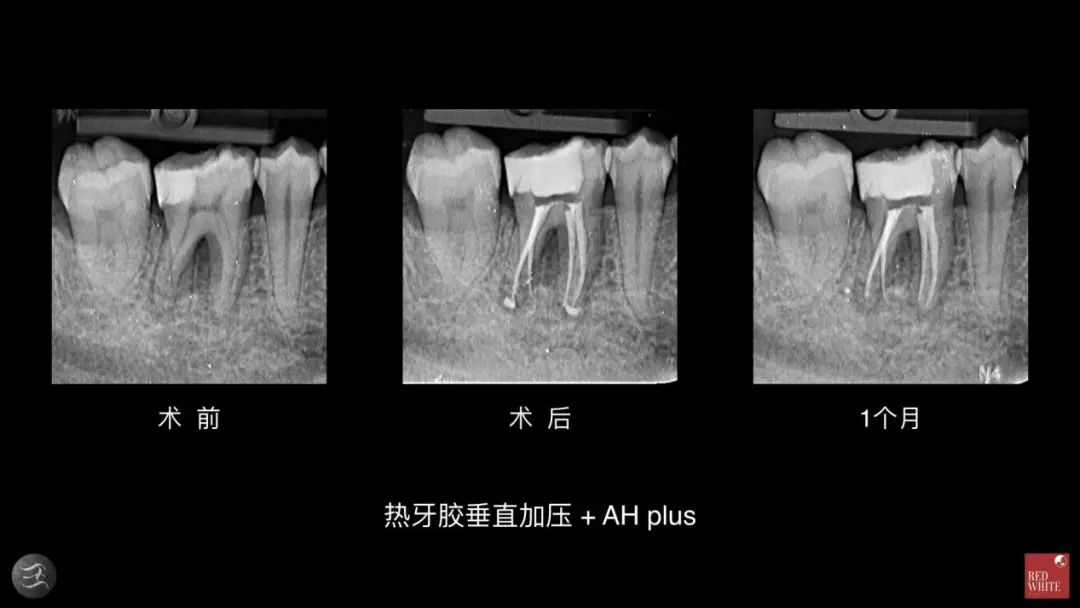

糊剂:收缩,容易被吸收,缺乏粘接性

从上面的案例可以看出,术后糊剂从根尖口外被挤出,1个月后超出的糊剂居然完全不见了。超出去的糊剂是在组织液这个湿润的环境里,对于树脂类糊剂是无法在湿润的环境中进行正常的反应和固化的。后期实验证明,连在根尖内的糊剂也会被吸收。实际的临床操作中,很难让根尖完全干燥,所以状态不稳定并会对机体产生刺激。